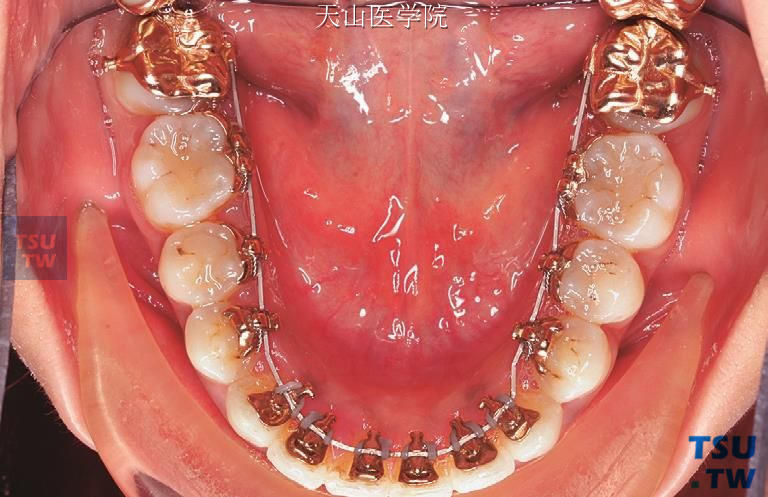

9日本的Fujita医生1979年发明了舌侧矫治器并提出了蘑菇形舌侧弓丝。由于尖牙和第一前磨牙厚度存在较大差异,正常牙弓舌侧形态为蘑菇形。在上颌牙弓尤其明显,需要在尖牙远中弯制

8由于使用0.018英寸系统舌侧托槽,较唇侧矫治技术,需使用较细、较柔软的弓丝进行舌侧正畸治疗。舌侧矫治由于牙体舌面解剖结构的不规则性,很难模仿唇侧技术实现“直丝&rdquo

6包括不锈钢丝、镍钛丝以及TMA丝。一般在排齐阶段应用镍钛丝,也可以应用不锈钢圆丝;在关闭间隙阶段可以应用不锈钢方丝通过滑动法关闭间隙,也可以应用TMA丝应用关闭曲法关闭间隙